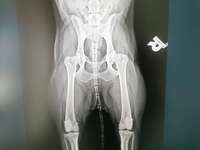

Guten Abend,mein Goldendoodle 15 Monate alt hat gerade Giardien. Sind mitten in der Panacur Therapie. Haben 5 Tage Panacur gegeben und dann 3 Tage Pause und ab morgen nochmal 5 Tage,dann 10 Tage Pause und der TA empfiehlt noch eine weitere Kur.

Meine Frage, im Mai wäre Buddy mit der jährlichen Impf ...